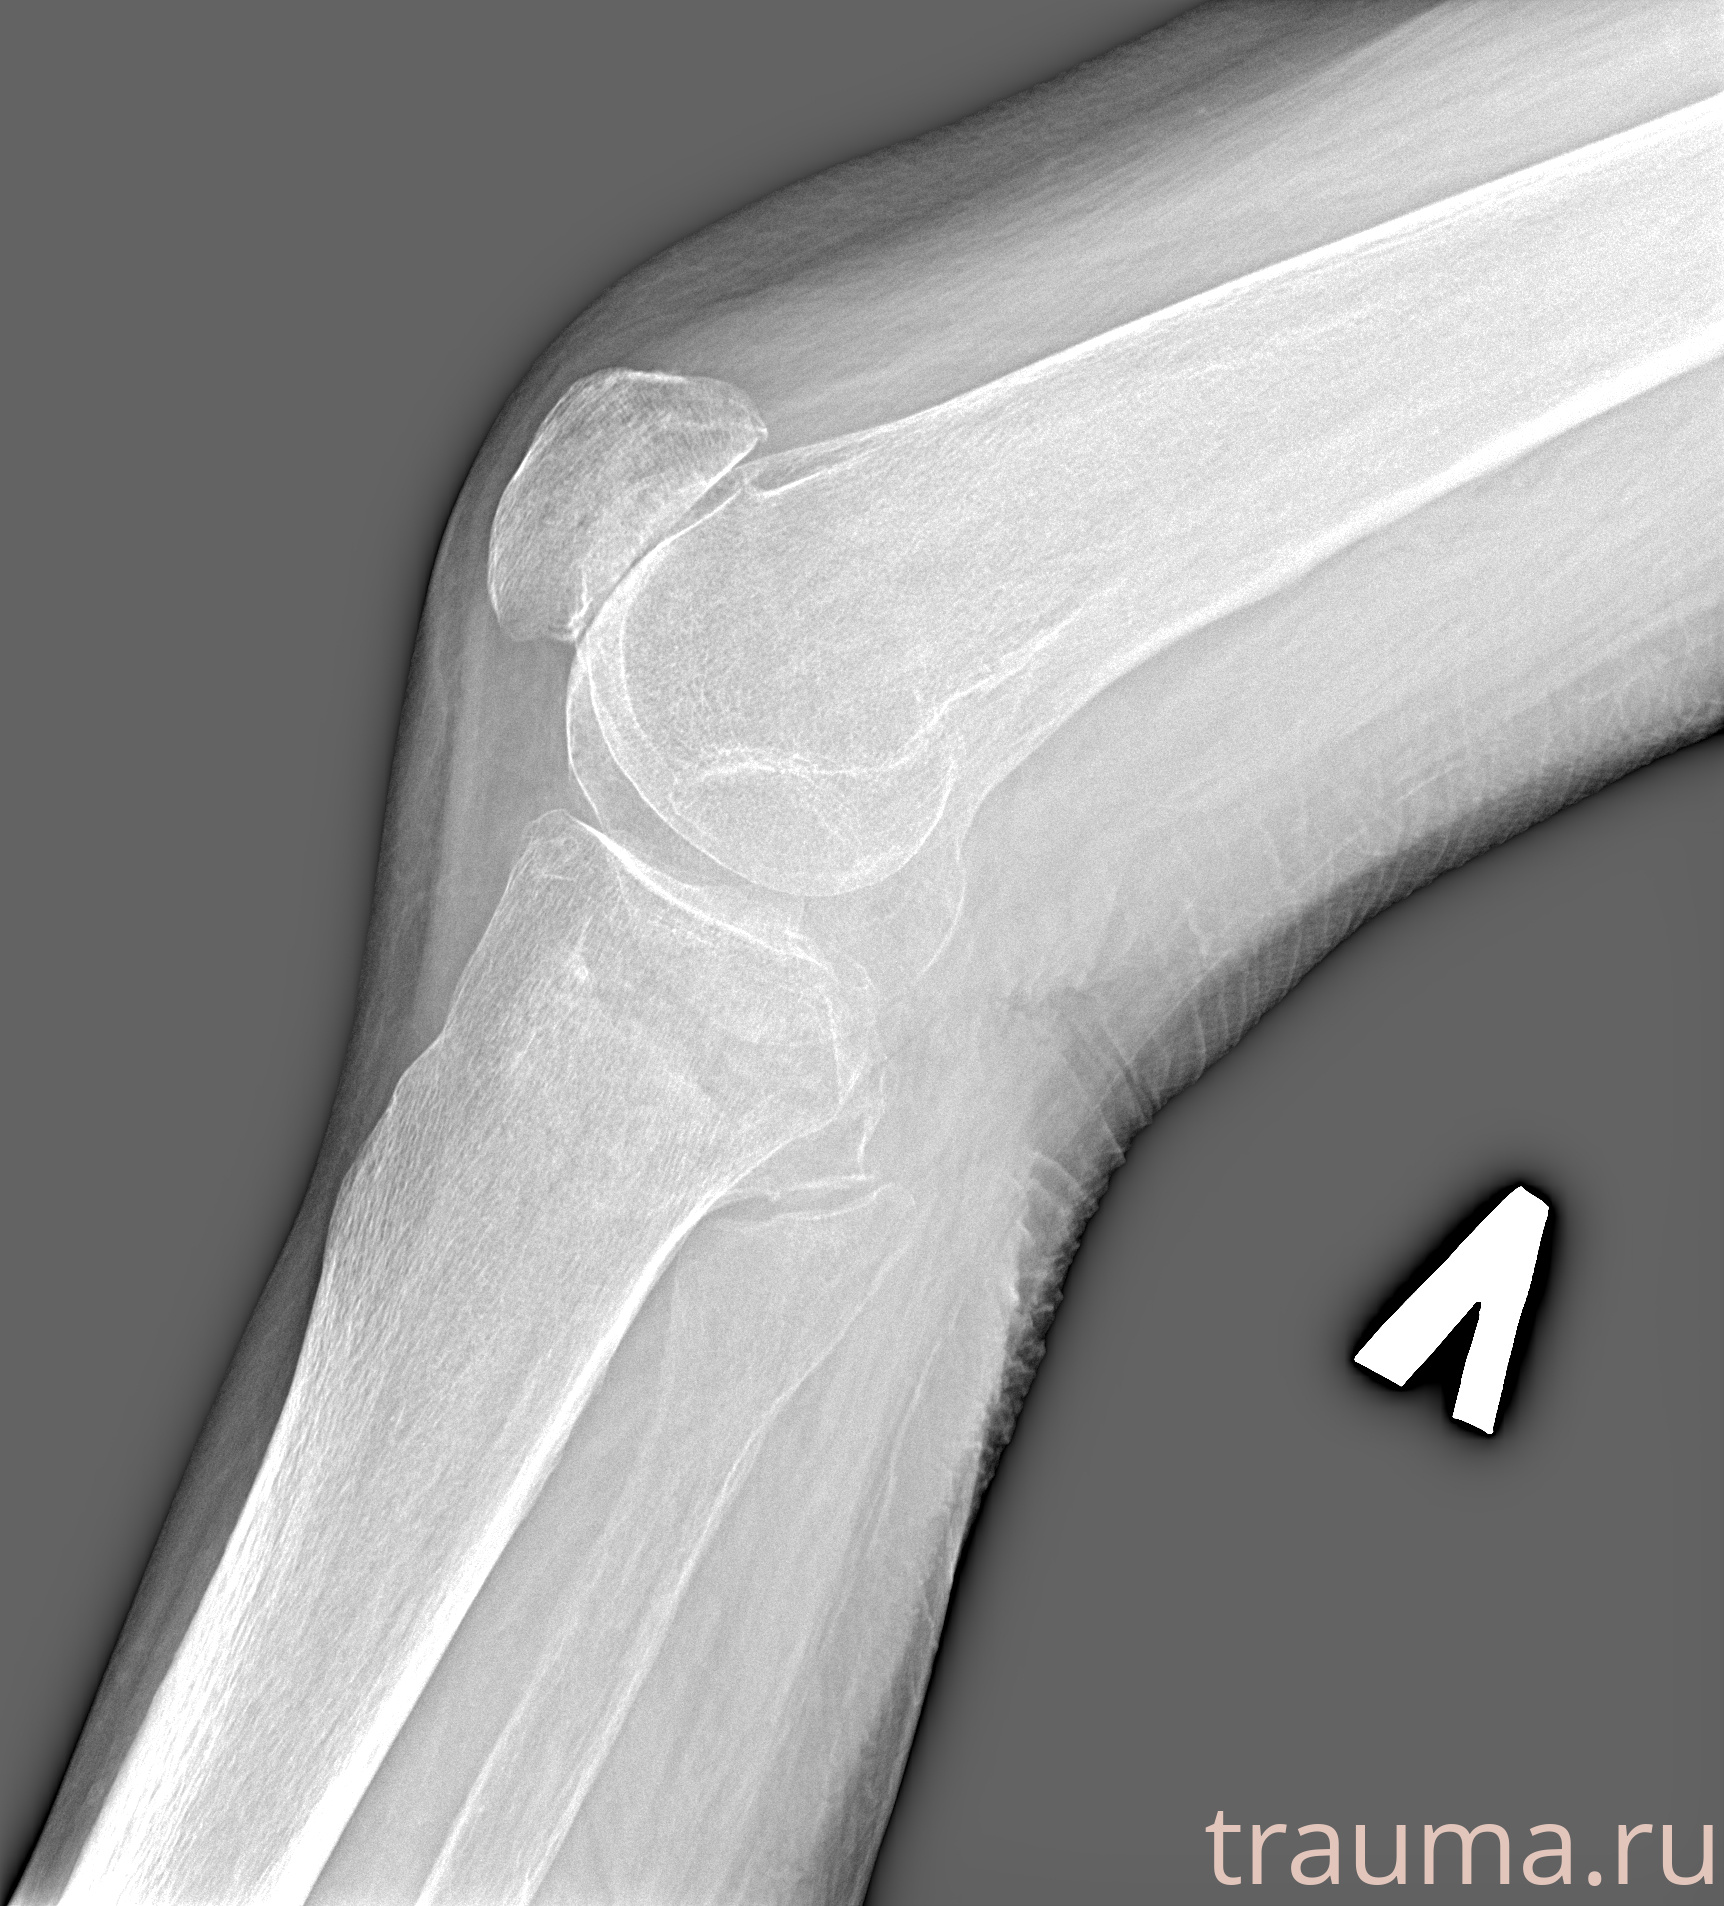

Рентгенограммы